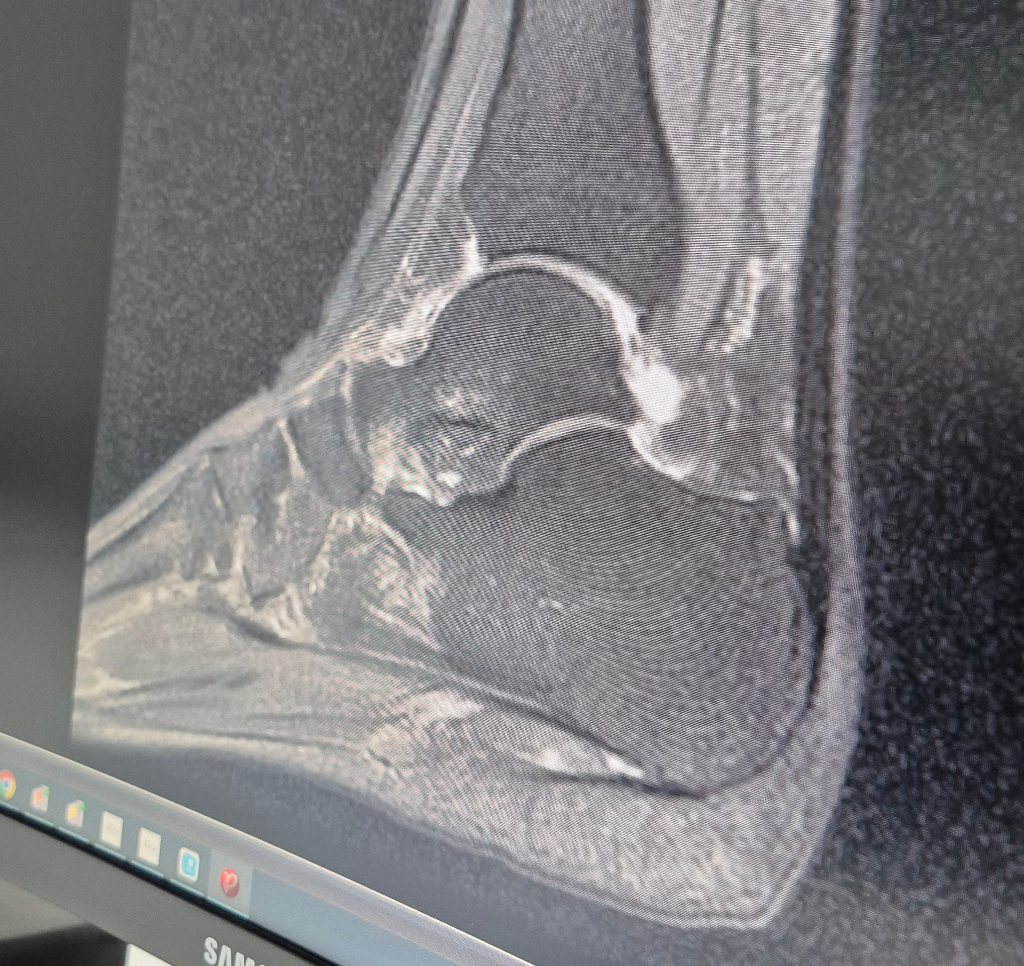

mri 거골 골절진단 상태가 어느 정도인가요?

mri는 15일 찍었어요 반깁스상태인데 오른쪽 발목 안쪽이 걸을때마다 아픈데 언제 쯤 괜찮아질까요?

올려주신 MRI사진상 거골에 경미한 골수부종 의심소견이 보입니다.

하지만 MRI의 다른 시퀀스 사진이 있어 올려주신 사진만으로 진단하기에는 어렵습니다.

사진을 찍으신 병원에서 자세한 MRI 결과 및 주치의의 설명을 참고하시기 바랍니다.